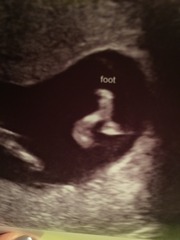

Scan was lovely this evening. Sonographer took lots of time to show us all everything. All looking good.

Congrats on your scans Sophia and Elle! Elle those pictures are just amazing, those little feet, wow!